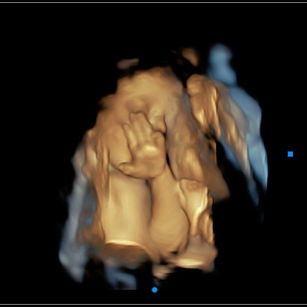

32 Weeks Pregnant

Muscles: Getting stronger, and movements may feel more forceful.

Movements

Space in the womb is getting tighter, but your baby is still very active. You’ll notice more rolling, stretching, and shifting than sharp kicks.